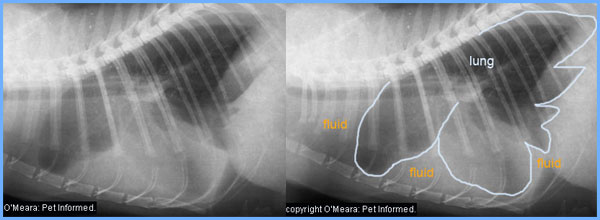

5b) Chest radiographs (x-rays).